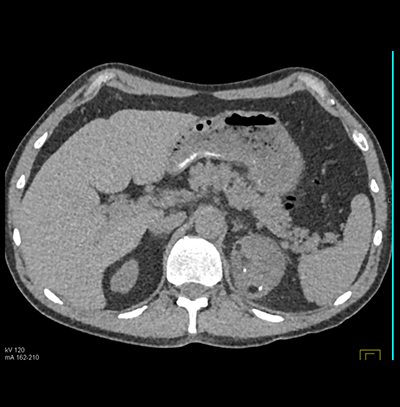

The workup for the patient incidental left adrenal mass is?

laparascopic adrenalectomy

CT or Ultrasound guided biopsy

an adrenal protocol CT

lesion is benign with no need for routine folllow-up